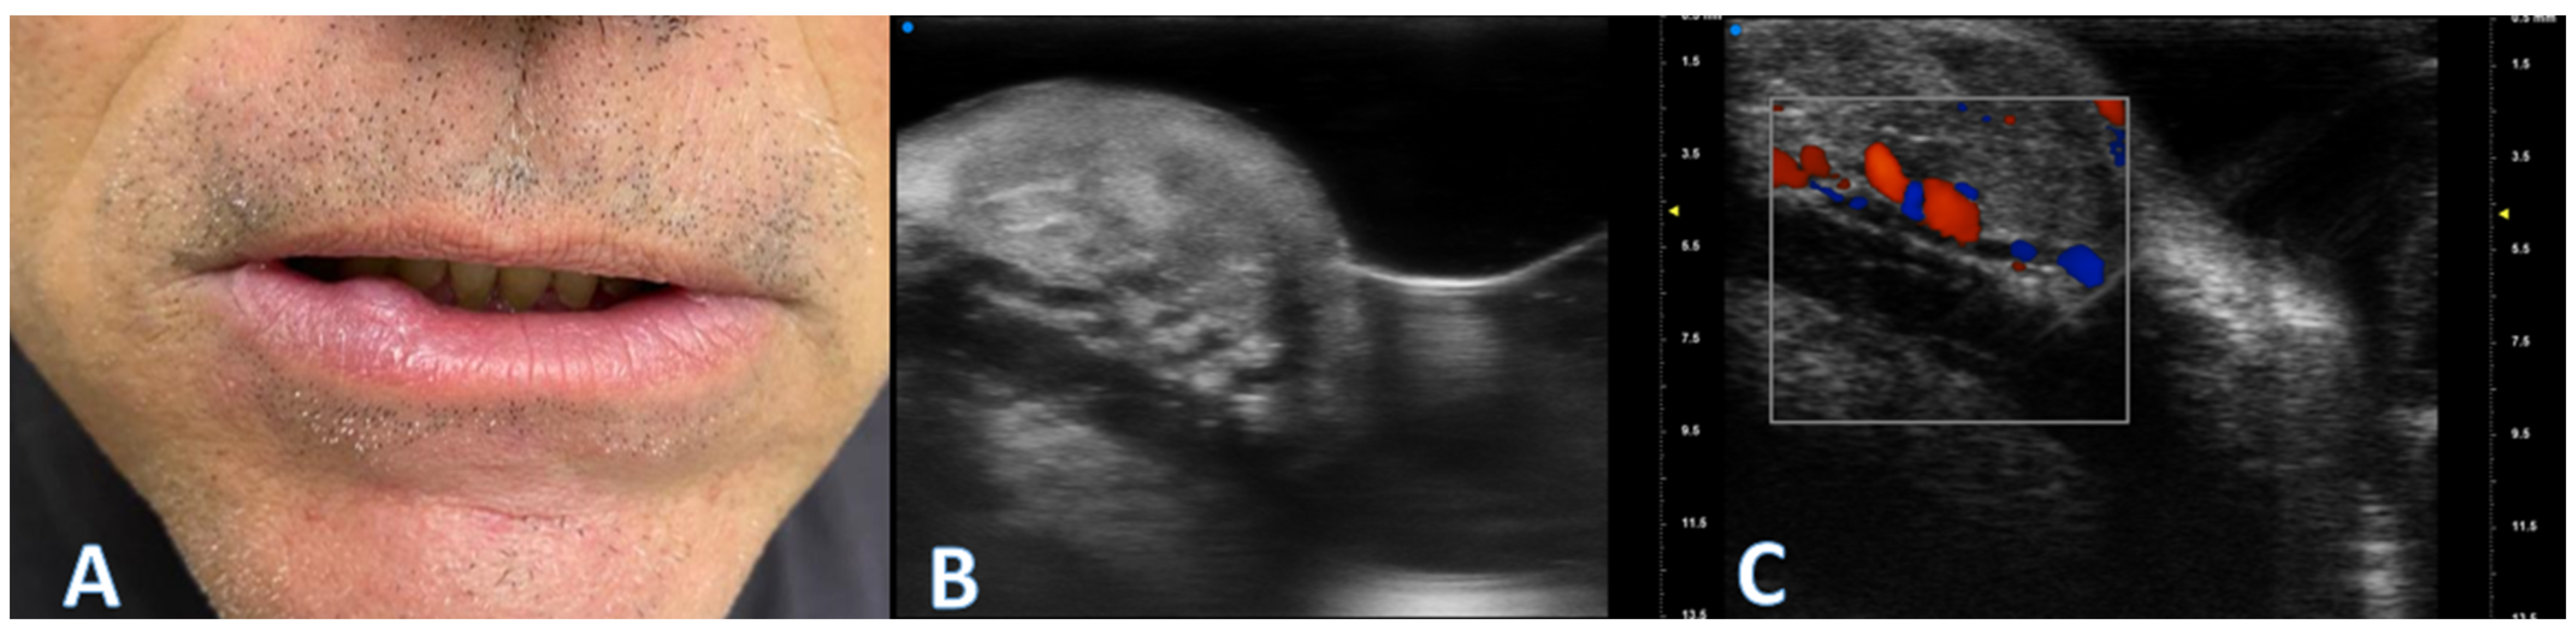

2.2. UHFUS Scan Protocol